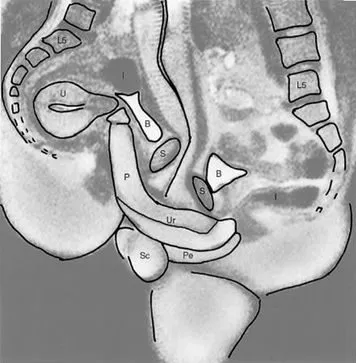

എം.ആർ.ഐ മെഷീനുകൾ ആദ്യമായി ഉപയോഗിച്ചു തുടങ്ങിയ കാലമായിരുന്നു അത്. അതുകൊണ്ടുതന്നെ വ്യക്തമായ ചിത്രങ്ങൾ ലഭിക്കാൻ ഏറെ സമയമെടുത്തിരുന്നു. കൺട്രോൾ റൂമിൽ നിന്നും നിർദ്ദേശം ലഭിക്കുന്നതുവരെ ചിലപ്പോൾ മിനിറ്റുകളോളം ഒരേ പൊസിഷനിൽ തന്നെ ദമ്പതികൾക്ക് തുടരേണ്ടി വന്നിട്ടുണ്ട്. വളരെ ഇടുങ്ങിയ, വെറും 50 സെന്റീമീറ്റർ മാത്രം വ്യാസമുള്ള ആ ട്യൂബിനുള്ളിൽ സാധാരണ ഗതിയിലുള്ള (missionary) പൊസിഷനുകൾ സാധ്യമായിരുന്നില്ല. അതിനാൽ വശങ്ങളിലേക്ക് ചരിഞ്ഞുകിടന്നുള്ള (spooning) രീതിയാണ് ഇവർ തിരഞ്ഞെടുത്തത്.

ലോകത്തെ അമ്പരപ്പിച്ച കണ്ടെത്തലുകൾ

1999-ൽ പ്രശസ്തമായ ബ്രിട്ടീഷ് മെഡിക്കൽ ജേർണലിൽ (BMJ) ഈ പഠനത്തിന്റെ ഫലങ്ങൾ പ്രസിദ്ധീകരിച്ചു. വൈദ്യശാസ്ത്രരംഗത്ത് വലിയൊരു തിരുത്തലായിരുന്നു ആ പഠനം. ഡാവിഞ്ചിയുടെ കാലം മുതൽ വിശ്വസിച്ചുപോന്നിരുന്ന പല ധാരണകളും ഈ എം.ആർ.ഐ ചിത്രങ്ങൾ തിരുത്തിക്കുറിച്ചു. ലൈംഗികബന്ധ സമയത്ത് പുരുഷലിംഗം ഒരു ‘ബൂമറാങ്ങിന്റെ’ (Boomerang) ആകൃതിയിലേക്ക് വളയുന്നുണ്ടെന്നും, അല്ലാതെ അത് നേരായ സിലിണ്ടർ ആകൃതിയിലല്ല നിലകൊള്ളുന്നതെന്നും എം.ആർ.ഐ സ്കാനിംഗിലൂടെ തെളിയിക്കപ്പെട്ടു. ഇത് പുരുഷന് വേദനയുണ്ടാക്കാതെ തന്നെ സ്ത്രീയുടെ യോനിയുടെ ആകൃതിക്കനുസരിച്ച് വളയാൻ സഹായിക്കുന്നു. കൂടാതെ, ലൈംഗിക ഉത്തേജന സമയത്ത് സ്ത്രീകളുടെ ഗർഭപാത്രത്തിന്റെ വലുപ്പം വർദ്ധിക്കുന്നില്ല എന്ന പുതിയ വിവരവും ഈ പഠനം ശാസ്ത്രലോകത്തിന് നൽകി.